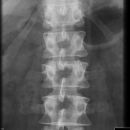

Wirbelsäule